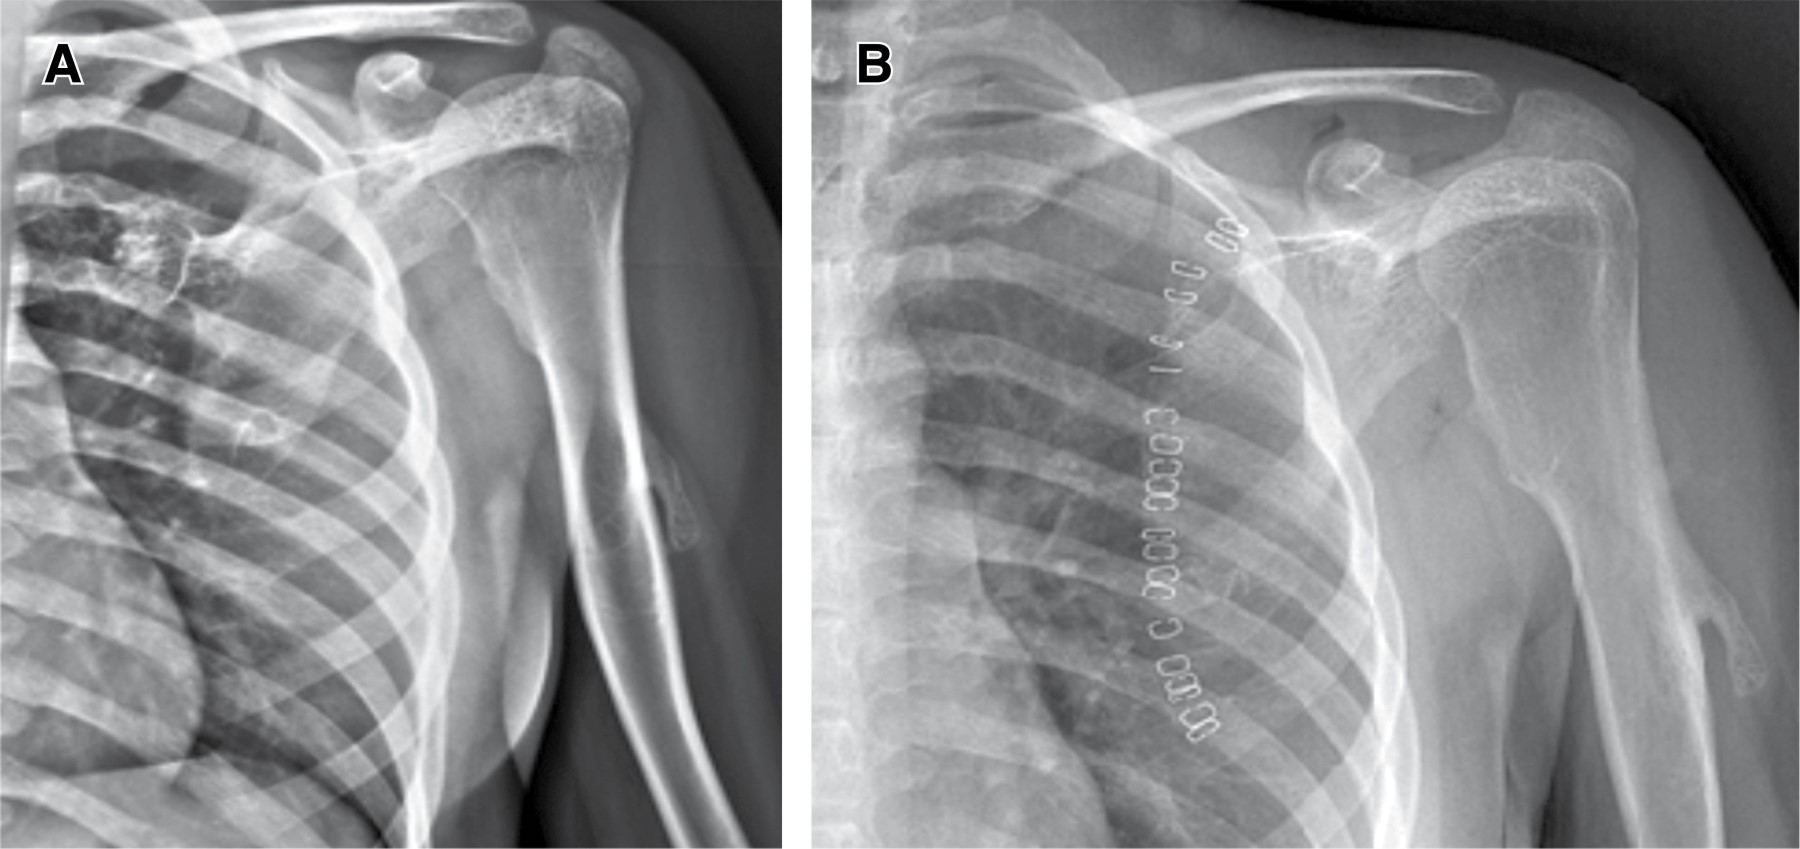

Fue programada el día 30 de enero de 2019 para resección de osteocondroma subescapular izquierdo (Figura 1), con valoración anestésica de IE (ASA I= paciente sano, E= cirugía de emergencia), sin contraindicación quirúrgica. Se coloca en decubito prono, bajo efectos de anestesia general balanceada (Figura 2), se realizó asepsia y antisepsia de extremidad torácica derecha y espalda, con posterior colocación de campos estériles con delimitación de sitio quirúrgico. Se realizó abordaje paraespinal sobre la escápula con desinserción de músculo romboidal de la espina de la escápula y se disecó hacia media, con exposición de pedículo del osteocondroma, se desinserta de su cápsula hasta delimitar todo su tamaño, con posterior corte a la base del osteocondroma con el uso de sierra oscilante y presencia de sangrado mínimo (Figura 3).

Figura 1